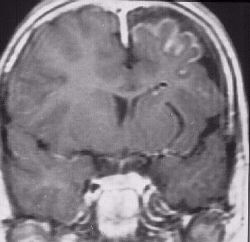

Refer to the above picture for question 4

4. The following are associated features:

Refer to the picture above for question 5

5. Associated features for the above condition include :